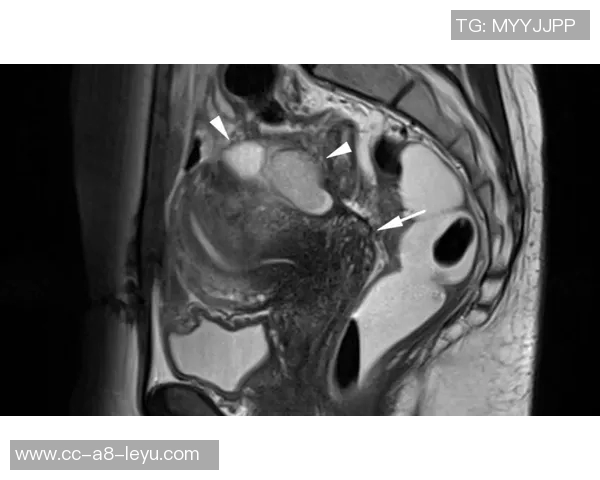

幸运的是,通过X光结果显示并未发现明显异常,这意味着目前没有骨折或严重损害的迹象。然而,这并不代表他完全没有危险,因为软组织损伤如韧带扭伤等问题仍然需要进一步确认。因此,医生建议进行MRI检查以获得更详细的信息。

MRI(磁共振成像)是一种无创性的高分辨率影像学技术,可以清楚地显示软组织结构,因此对于评估肌肉、韧带和其他组织的损伤尤为重要。这也是为什么医生会选择第二次检查,以确保全面了解约维奇的实际情况。